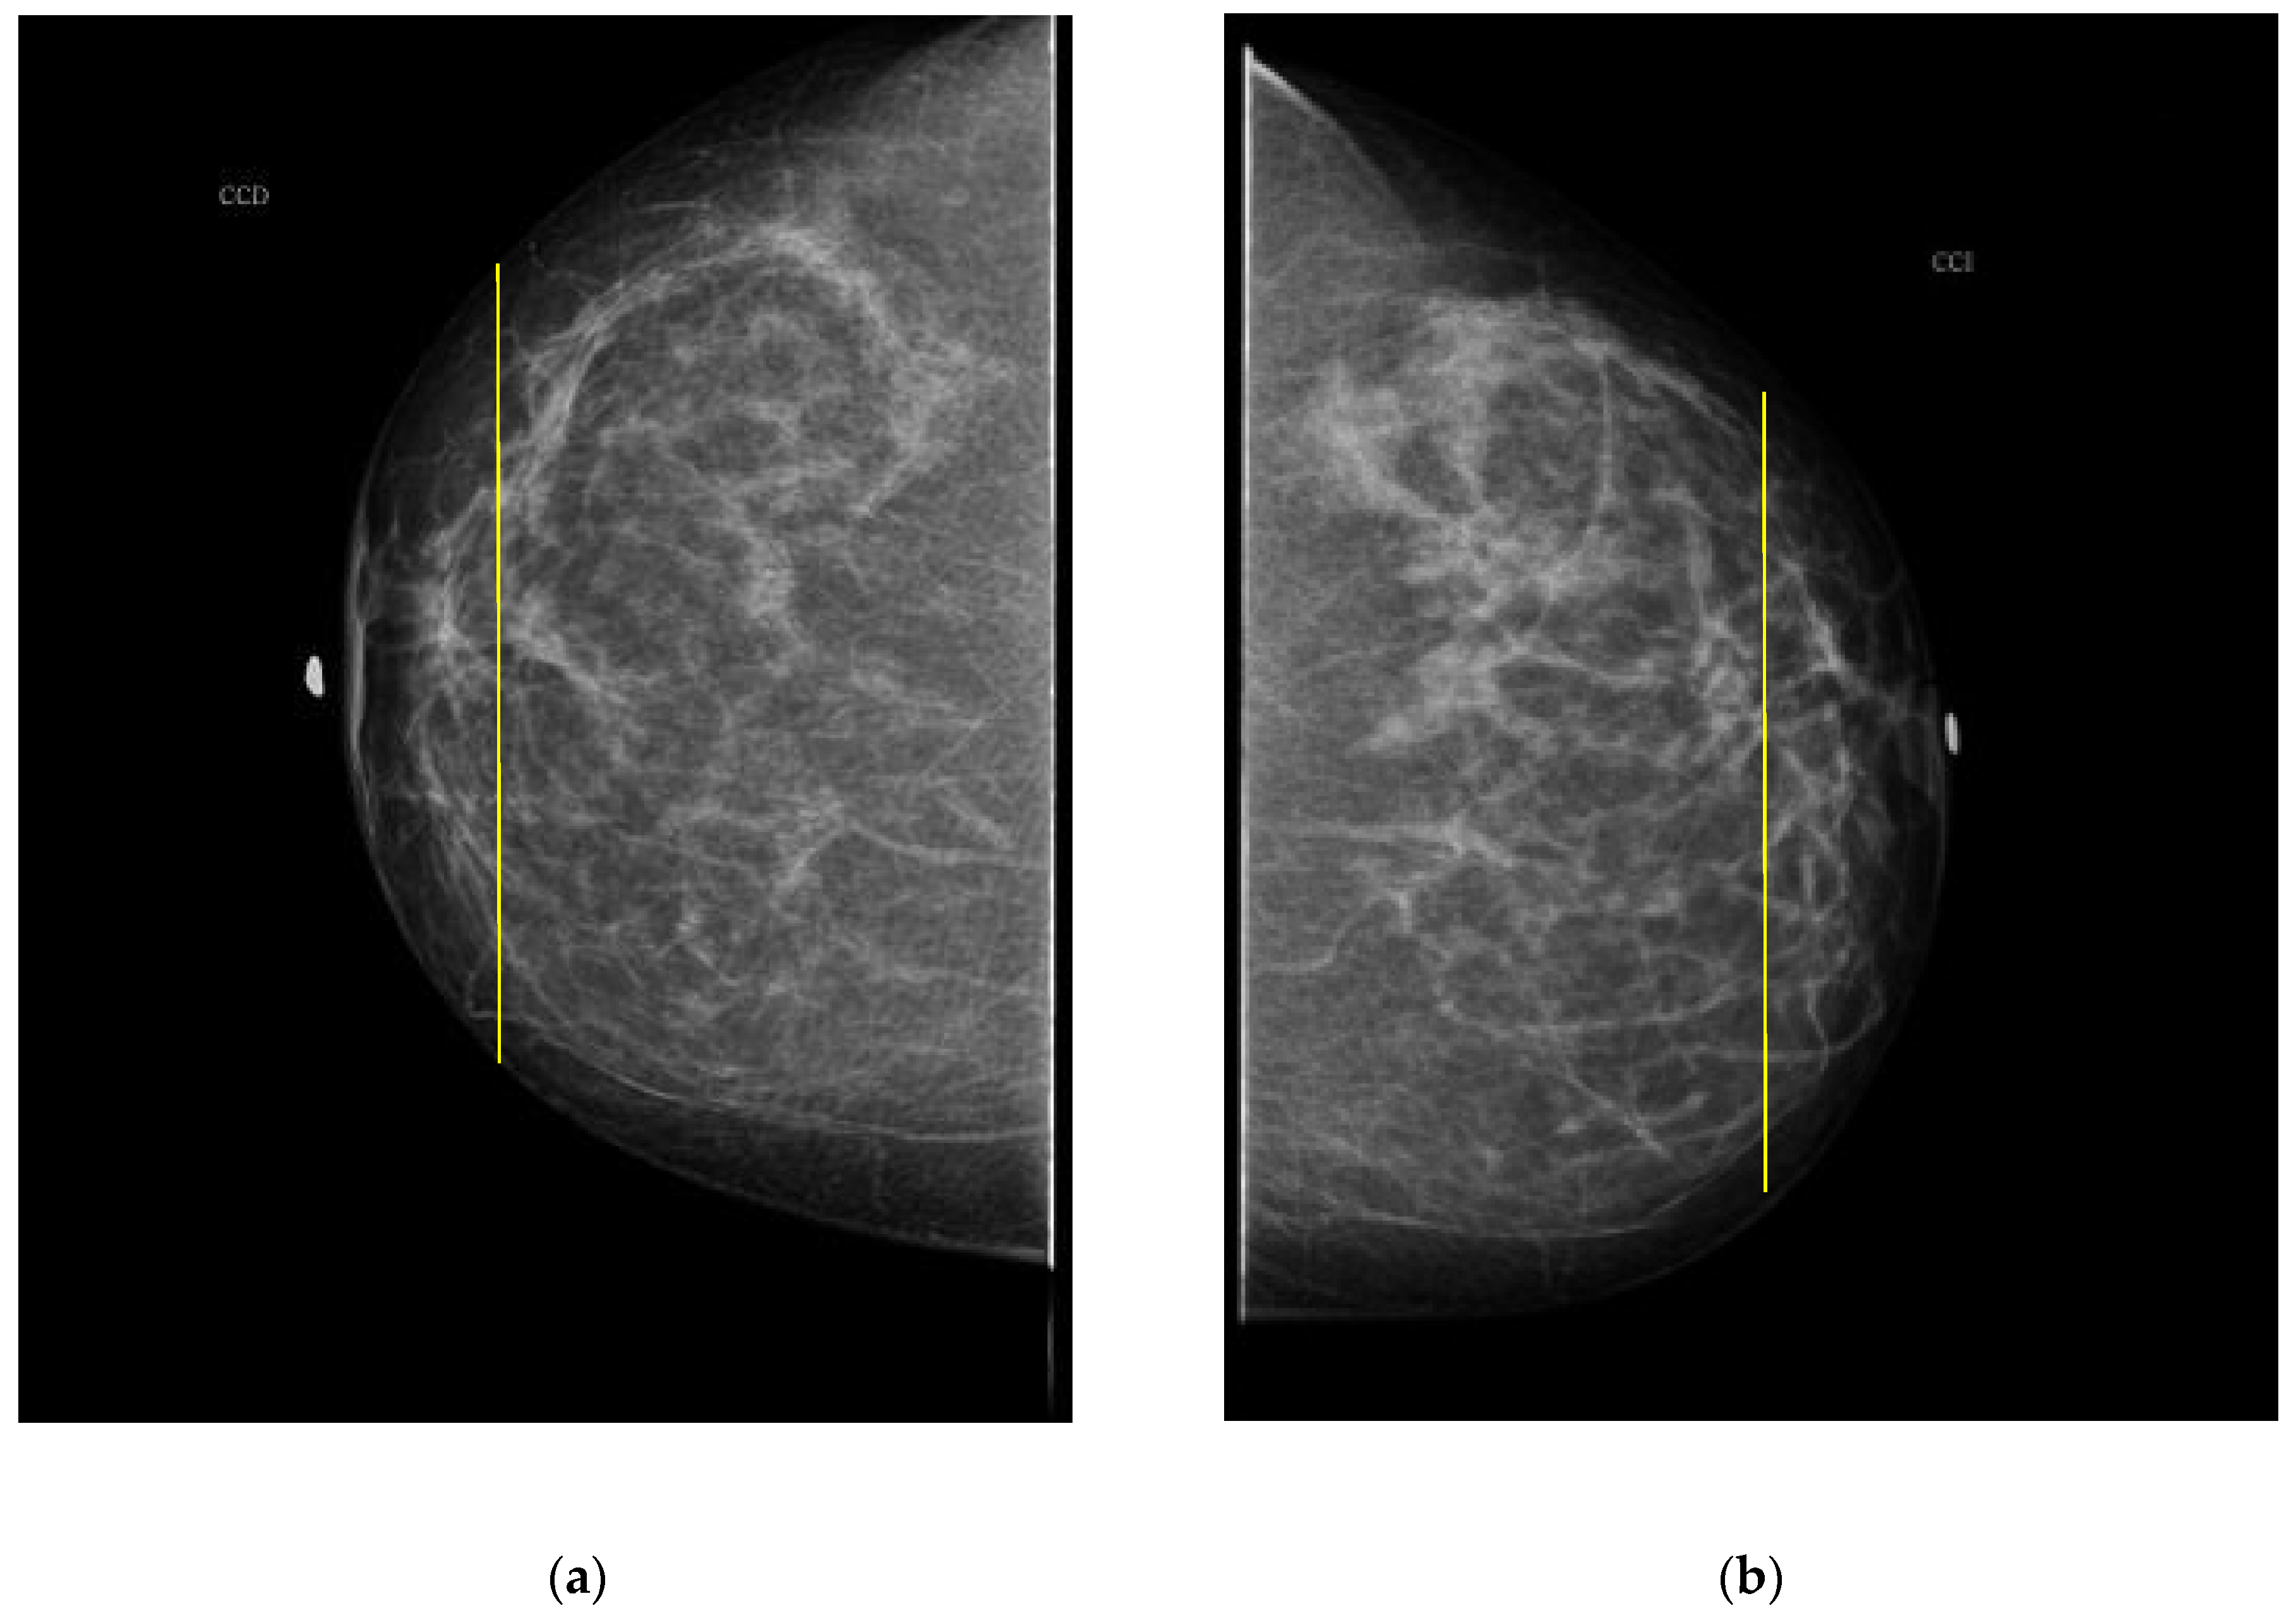

As it is noted, the same BI-RADS PBD for both breasts in all the participants was obtained by the specialist; meanwhile, a 61.5% was achieved by the described ATC clustering. An important uncertainty factor to be considered is that the electrodes ring position in most of the cases is not exactly the same on both breasts for each participant. As a consequence, different bioimpedance values are measured because the breast tissue distribution is not the same. For instance, the specialist evaluation for both breasts in participant 9 is BI-RADS c, while the described ATC classification resulted in BI-RADS b-c and c for the right and left breast, respectively. Such difference may be explained by analyzing the relative electrode ring positions on both breasts. The CC mammogram images of both breasts are shown in Figure 6, where the electrodes ring position is illustrated with a yellow vertical line. As it is observed, the left breast has less adipose tissue than the right breast. This amount of fatty tissue is the reason why a higher bioimpedance value is measured.

Figure 6. CC mammogram images of participant 9 and relative electrode ring position (yellow vertical line): (a) right breast; (b) left breast.